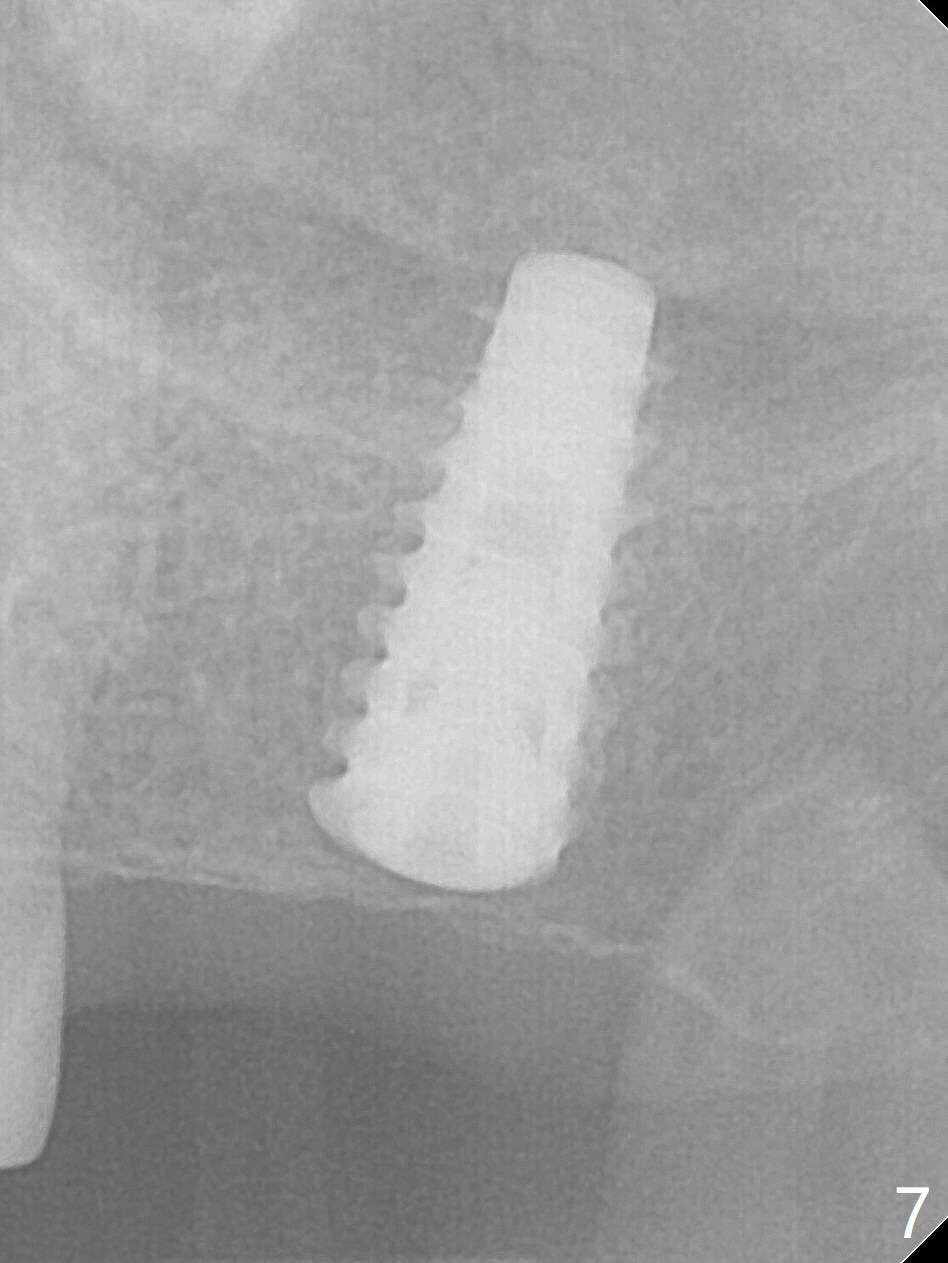

The ridge is pointed at the site of #15 (Fig.1). A 1.2 mm initial drill is used to start osteotomy for 10 mm, followed by an incision over the ridge mesiodistally for ~ 8 mm. After tapping the #15 C blade, the 1st Bone Expander 1.0/1.6 mm) is inserted for ~ 11 mm (Fig.2, 20 Ncm). Bone expansion continues until #4 Expander (2.4/3.7 mm, Fig.3). When 4x11 mm and 4.5x11 mm dummy implants are placed (Fig.4), insertion torque remains 20 Ncm. Following placing allograft with 3-4 amalgam carriers, a 5x11 mm IBS implant is placed with 20 Ncm (Fig.5,6). In fact the implant turns when an abutment is placed. When the implant is re-inserted, torque decreases to 10 Ncm. Instead a healing screw is placed. The low torque value is due to soft bone and failure to underprep. #4 Expander (Fig.3) seems larger than 4.5 mm implant (Fig.4). #3 Expander (1.7/3.1 mm) should have been used prior to definitive implant placement. The implant appears to have osteointegrated 3 months postop (Fig.7); impression is taken. The bone density at the crest increases 1.5 years post cementation (Fig.8 *, as compared to Fig.6), although there is mild bone loss. Implant placement should be deep when bone expansion is carried out. The tooth #14 develops a buccal fistula, corresponding to periapical radiolucency of the mesiobuccal root (Fig.9 white >). The abutment of #15 may be incompletely seated (black <). PA taken when RCT of #14 is finished does not show the incomplete seating of the abutment (Fig.10). Since there appears no history of abutment screw loosening, the abutment is not reseated when #14 is prepared for crown. Recall 3 years 7 months post cementation shows incomplete seating of the abutment (Fig.11 >). After crown proximal reduction (Fig.12 *) and clockwise turn of the crown, the abutment appears to be completely seated. When the case returns from lab, the separate crown and abutment cannot be connected to the fixture because of soft tissue adaptation and change in a month. The abutment is reseated to the fixture analog in the model and the crown is recemented with temp bond (in case of misalignment) while making sure that the crown has the best proximal contact with the neighboring crown. With the abutment and crown in a unit, it is much easier to reseat the abutment with normal proximal contact. The torque is 20 Ncm. The access hole is closed with Cavit.